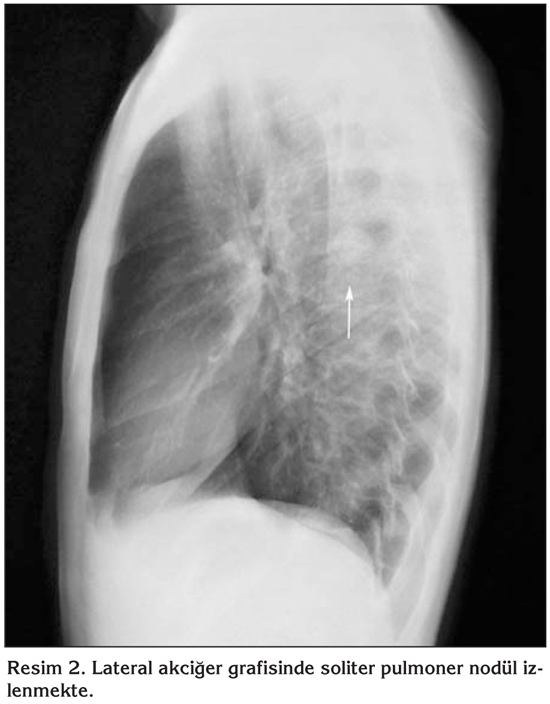

Yirmi ya??nda erkek hastan?n, alt? ayd?r halsizlik ve ?? ayd?r sol yan a?r?s? yak?nmalar? vard?. Askerlik g?revini yapmakta iken Verem Sava? Dispanseri taraf?ndan yap?lan taramada ?ekilen PA akci?er grafisinde ku?kulu lezyon saptanmas? ?zerine hastanemize sevk edildi. Fizik muayene bulgular? normal saptand?; hastan?n ate?i; 36?C, nabz?; 63 vuru/dakika, TA; 100/65 mmHg, solunum say?s?; 16/dakika idi. ?z ge?mi?inde ve yak?n aile anamnezinde bir ?zellik yoktu. Bir paket/y?l sigara ?yk?s? vard?. Tam kan, tam idrar, sedimentasyon ve rutin biyokimya incelemeleri normal s?n?rlarda tespit edildi. PA ve lateral akci?er grafilerinde sol hemitoraksta ?st zonda SPN ile uyumlu g?r?n?m mevcuttu (Resim 1,2). Toraks bilgisayarl? tomografi (BT)'de; sol akci?er ?st lob apikoposterior segmentte, periferik yerle?imli, yakla??k 2 x 2 cm ?ap?nda, d?zg?n kont?rl?, sferik SPN ile uyumlu g?r?n?m saptand?. Mediastende patolojik boyutlarda lenfadenopati yoktu ve tan?mlanan g?r?n?m haricinde infiltrasyon ve kitle saptanmad? (Resim 3). Hasta balgam ??karamad??? i?in al?nan mide suyu asido-alkalo rezistan basil (ARB) negatif olarak de?erlendirildi ve k?lt?r?nde ?reme olmad?. Bronkoskopide endobron?iyal lezyon g?zlenmedi. Bron? lavaj? ARB negatifti ve k?lt?r?nde ?reme olmad?. Bron? lavaj? sitolojik incelemesi malignite y?n?nden negatif olarak raporland?. Kist hidatik i?in yap?lan ELISA testi negatif bulundu. Bat?n ultrasonografi (USG) incelemesi normaldi. Olgudan SPN etyolojisini ayd?nlatabilmek i?in g???s cerrahisi kons?ltasyonu al?nd? ve olguya kist hidatik ?n tan?s?yla operasyon planland?. Torakotomi ile sol ?st lobda saptanan 2 x 2 cm'lik nod?le wedge rezeksiyon uyguland? ve perioperatif patoloji kons?ltasyonu istendi. Elde edilen materyalin makroskobik incelenmesinde malignite saptanmamas? ?zerine operasyon sonland?r?ld?. Eksizyonel biyopsi ?rne?inin mikroskobik incelemesi intralober pulmoner sekestrasyon (Kesitlerde akci?er parankimi bulgular? g?steren iyi s?n?rl? nod?ler lezyon izlenmektedir. G?m??leme y?ntemiyle yap?lan incelemede lezyonda yayg?n olarak retik?lin liflerinde art??, baz?lar? hiperplastik g?r?n?mde damar yap?lar? ve d?zensiz bron? alveol ?at?lar? g?r?lmektedir) olarak raporlanm??t?r.

Resim 2